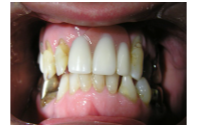

2) Anterior view with denture